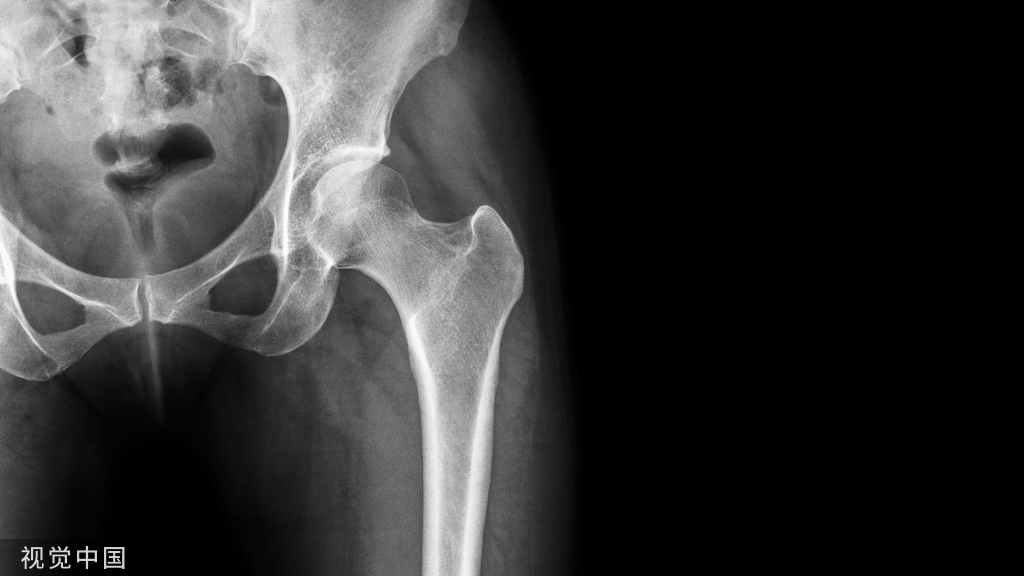

闭合复位的入路为“复位切口"(图6A、B)。

复位切口的位置至关重要(图6B)

复位切口的位置应位于外科颈水平,结节间沟后方1cm处。

使用透视确认外科颈水平(图6C、D)。